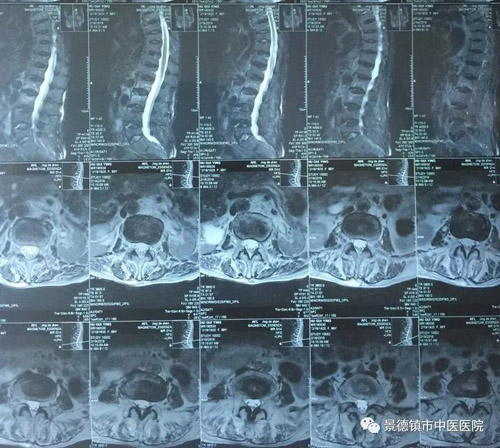

上圖為百歲老人手術前的影像學資料

我院骨二科在2019年2月20日,收治了一名百歲的女性老年人入院,MRI提示“L2、L3椎體壓縮性骨折”。既往有重度高血壓、糖尿病史,心肺功能差,且脊柱嚴重畸形,無法耐受俯臥位體位。骨二科及時邀請麻醉科會診,經過全面縝密的考慮,綜合老人的全身情況和代償能力、手術的等級,擬選擇的麻醉方式來評估麻醉風險并擬定了詳細具體的麻醉方案。